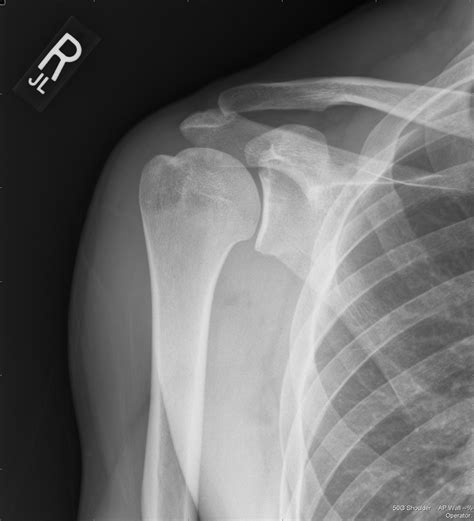

Interpreting a Shoulder Xray Normal

When a radiologist reviews a shoulder X-ray, they look for specific features that indicate a normal shoulder joint. These features include:

• Alignment of Bones: The humeral head should be properly aligned with the glenoid fossa of the scapula.

• Bone Density: The bones should have a uniform density without any areas of increased or decreased density.

• Joint Spaces: The joint spaces should be uniform and without any narrowing or irregularities.

• Soft Tissues: The soft tissues around the joint should appear normal without any swelling or abnormalities.

If all these features are present, the X-ray is considered Shoulder Xray Normal.

Common Findings in a Shoulder Xray Normal

A normal shoulder X-ray typically reveals the following:

• Humeral Head: The head of the humerus should be round and well-defined, sitting snugly in the glenoid fossa.

• Glenoid Fossa: The glenoid fossa should be smooth and without any erosions or irregularities.

• Acromioclavicular Joint: This joint should be well-aligned and without any signs of separation or dislocation.

• Clavicle: The clavicle should be intact and without any fractures or deformities.

• Soft Tissues: The soft tissues around the shoulder should appear normal, with no signs of swelling or inflammation.